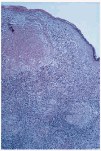

Esta lesión había sido biopsiada en cuatro ocasiones con similares hallazgos histológicos. El principal hallazgo era la presencia en toda la dermis de un denso infiltrado inflamatorio con granulomas constituidos por histiocitos epitelioides y células gigantes multinucleadas en su parte más central y linfocitos en periferia; en varios de ellos existían áreas de caseosis (figs. 2 y 3). Los linfocitos del infiltrado eran monomorfos sin atipias. Se detectaron focos aislados de epidermotropismo, sin franca atipia nuclear en los linfocitos; no se evidenciaron microabcesos de Pautrier; en algunas áreas existía fibrosis laminar en dermis papilar; en algunos cortes se evidenciaron áreas de mucinosis folicular; algunas células gigantes presentaban signos de linfofagocitosis. En el estudio inmuhistoquímico destacaba la expresión de CD3 y CD4 en el 80% del infiltrado linfocitario, del CD68 en las células epiteloides del centro de los granulomas y de la S100 en células dispersas dentro del infiltrado inflamatorio (no en células gigantes). No se observaron signos de elastólisis con la tinción de Van Gieson, ni cuerpos extraños con la luz polarizada, ni microorganismos con las tinciones de Ziehl-Neelsen y PAS. La visión directa de leishmanias, el cultivo para microbacterias y la PCR para Mycobacterium avium intracelulare, Mycobacterium tuberculosis y Mycobacterium leprae fueron negativas. No pudo realizarse estudio de reordenamiento genético.

Fig. 3. Detalle de los granulomas compuestos por linfocitos, células epiteliodes y células gigantes.